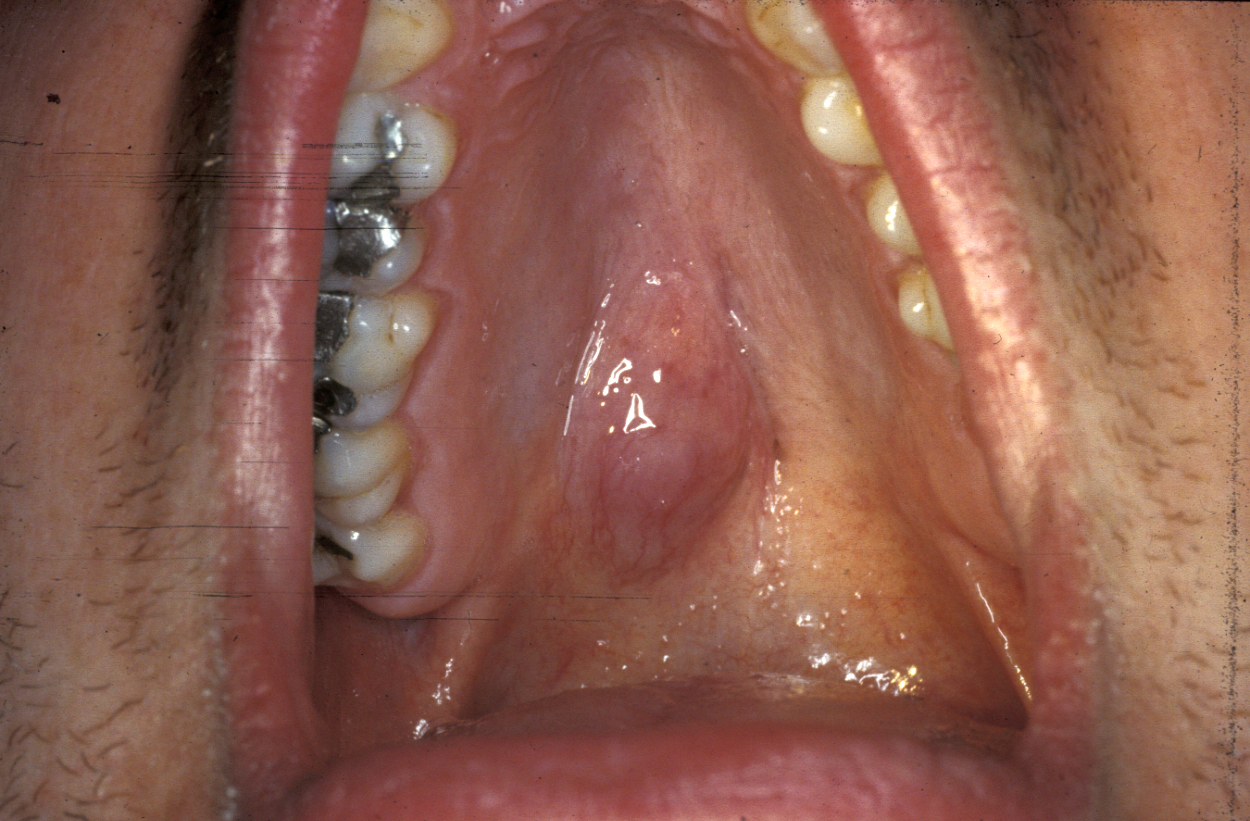

Another location where salivary gland pleomorphic adenoma may occur is in the palate area, most often at the junction of hard and soft palates (see Figure 7).

Figure 7: Palatal pleomorphic adenoma arising at a typical site.